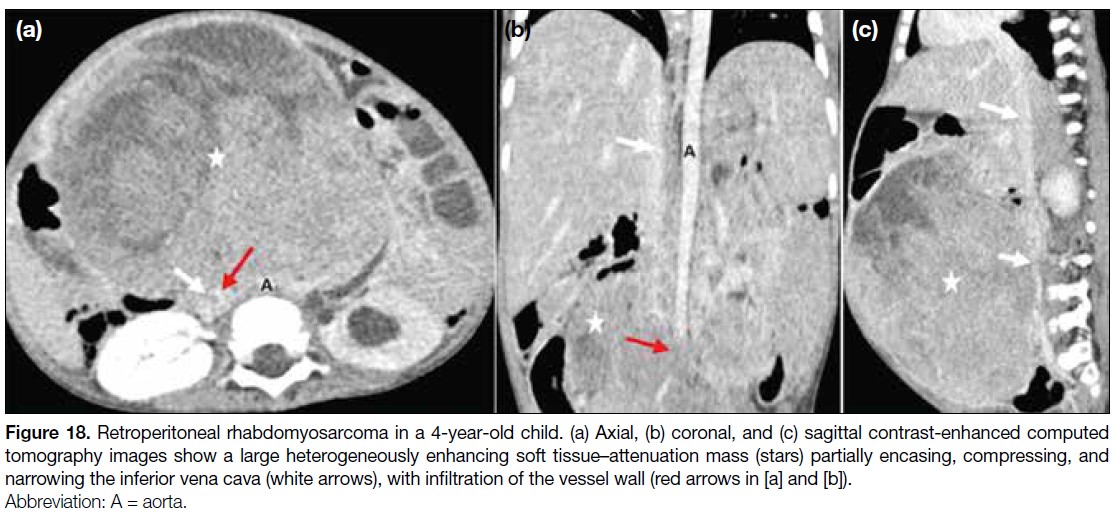

in hepatoblastoma (Figure 17). Retroperitoneal

malignancies in children may involve the abdominal

vasculature, including the IVC (Figure 18). Thrombosis

and vascular displacement are more common in Wilms

tumours than vessel encasement, whereas vascular

invasion occurs more frequently in neuroblastomas[4] (Figure 19).

Figure 18. Retroperitoneal rhabdomyosarcoma in a 4-year-old child. (a) Axial, (b) coronal, and (c) sagittal contrast-enhanced computed

tomography images show a large heterogeneously enhancing soft tissue–attenuation mass (stars) partially encasing, compressing, and narrowing the inferior vena cava (white arrows), with infiltration of the vessel wall (red arrows in [a] and [b]).